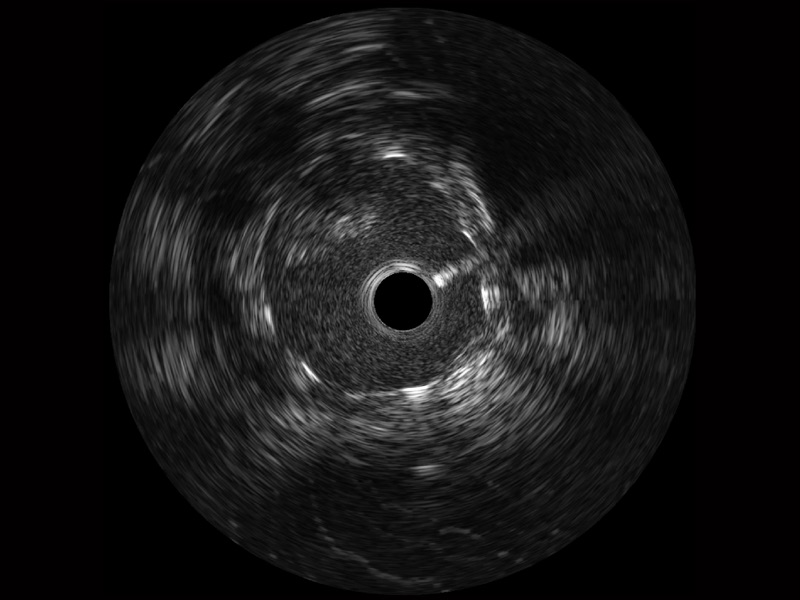

银河优越会宽频IVUS图像

对比传统IVUS导管成像,银河优越会宽频IVUS图像的近场支架梁显影更细腻,远场中膜外血管仍清晰可辨,兼顾远中近,兼顾分辨力与穿透深度